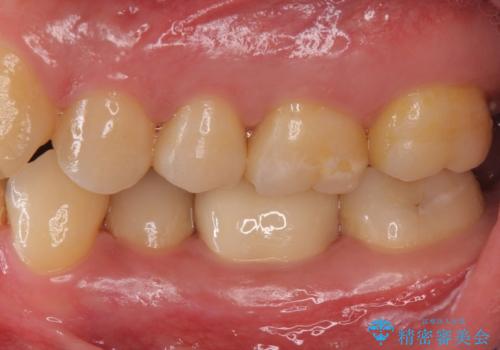

- 左下6 仮歯+セラミッククラウン 11000円+110000円費用は治療当時の料金となります

樹脂の材料はどうしても変色などの劣化スピードが速いです。

樹脂の変色が気になる場合は、劣化しにくいセラミックに材料ごと変えることをお勧めします。

セラミック治療の注意事項(リスク・副作用など)

- 天然歯を削ります

- 硬い素材は天然歯を傷つけてしまう場合があります

- かみ合わせや歯ぎしりが強すぎる方はセラミックが割れてしまう可能性があります

- 自費診療(保険適用外治療)となります